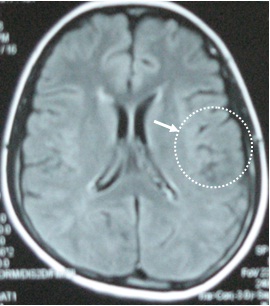

Chụp MRI sọ não phát hiện tại thuỳ thái dương trái có 3 khối u kích thước các khối 1,5 x 1,5 cm, ngoài ra còn có các u kích thước nhỏ xung quanh. Hình ảnh MRI gợi ý đến hình ảnh u Lympho não hơn là di căn não. Bệnh nhân được chỉ định mở sọ não lấy u làm giải phẫu bệnh nhưng bệnh nhân đã từ chối phẫu thuật.

VàoTrung tâm YHHN&UB, Bệnh viện Bạch Mai, bệnh nhân được chỉ định làm thêm xét nghiệm chuyên khoa Xạ hình bạch mạch với Fyton - Tc-99m (ghi hình với máy SPECT),

(Hình ảnh xạ hình bạch mạch bằng máy SPECT với

Fyton-Tc-99m )

Kết quả: phát hiện thấy có tổn thương hạch thượng đòn bên trái kích thước khá nhỏ (trên lâm sàng không sờ thấy được).

Tiến hành sinh thiết tổ chức thượng đòn (ST Daniel) lấy ra đựợc một hạch kích thước 0,6 cm, chắc, ranh giới rõ, gửi làm xét nghiệm giải phẫu bệnh , kết quả là U lympho ác tính không Hodgkin, tế bào lớn lan toả (WF7)

Bệnh nhân được tiến hành điều trị hoá chất phác đồ CHOP 8 đợt và tiêm Methotrexat nội tuỷ, kết quả u sọ não tan hoàn toàn. Đến nay, bệnh nhân đã được ra viện 10 tháng. Hiện tại vẫn khoẻ mạnh, chụp MRI sọ não không phát hiện ra khối u.

Đây là một ca lâm sàng hay, một tình huống chẩn đoán khó khăn, nhờ có kỹ thuật YHHN phát hiện tổn thương hạch thượng đòn mặc dù kích thước còn rất nhỏ, rất dễ bỏ sót bằng thăm khám lâm sàng. Bệnh nhân rất may mắn không phải chịu cuộc đại phẫu mở sọ não lấy u làm xét nghiệm giải phẫu bệnh mà vẫn có hướng điều trị đúng đắn.